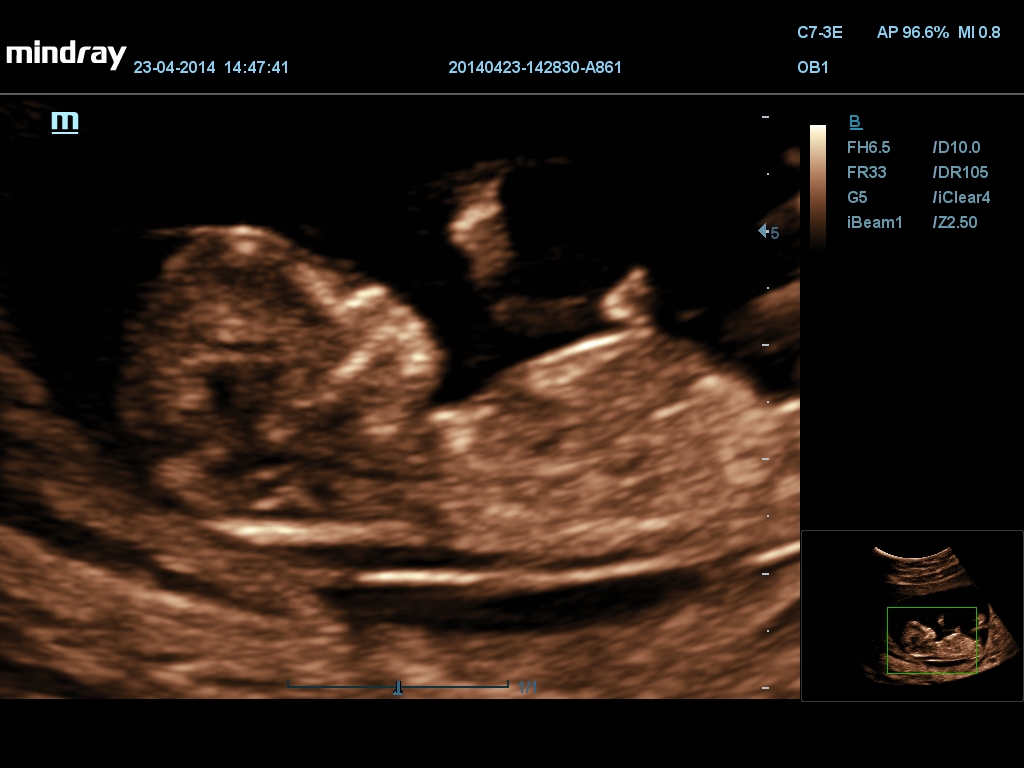

Mindray DC-70 Exp с технологией X-Insight – это узи-аппарат для высококачественной диагностики. Преимущества: высокая эффективность, точность визуализации, результат в «одно касание» с экспертными датчиками. Рекомендуется для государственных учреждений.